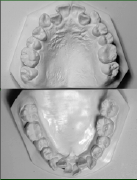

• 模型とその分析

• _